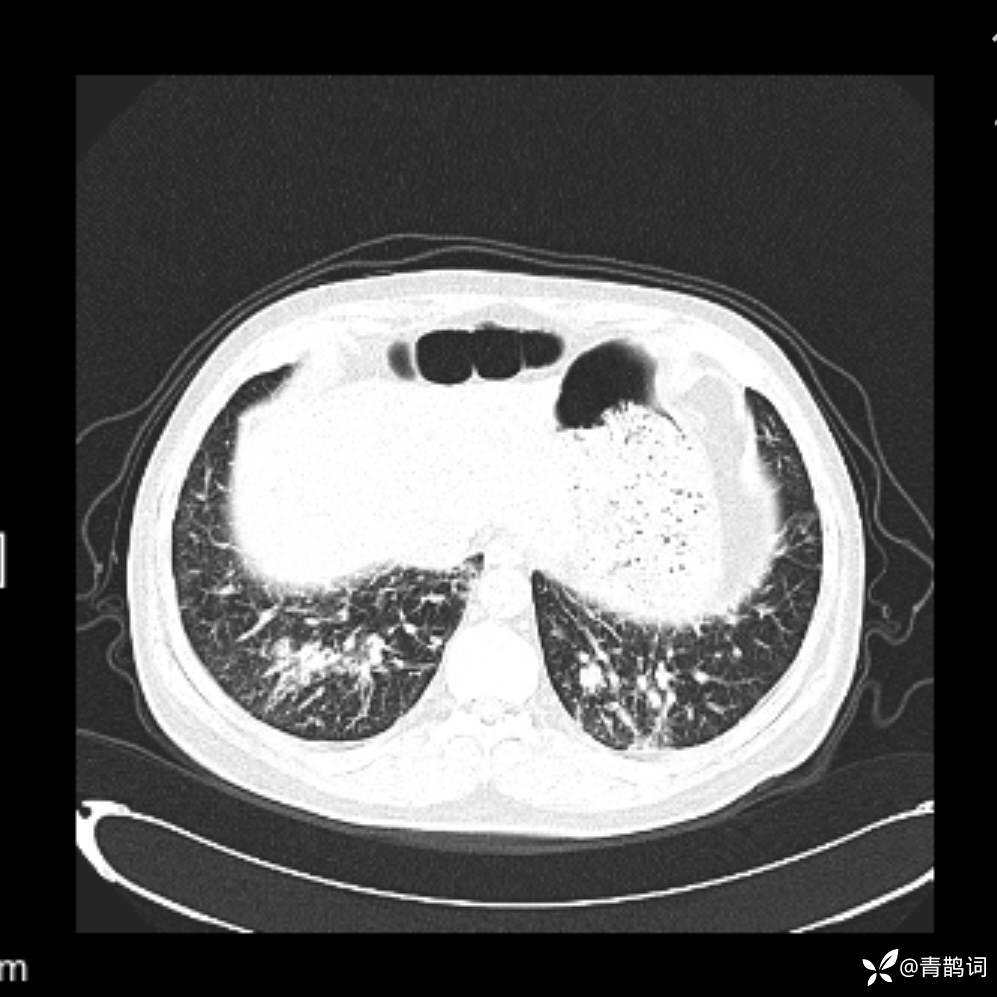

患者年龄:30岁。

患者性别:男。

简要病史:左颜面部肿胀2年,反复咳嗽咳痰,逐渐加重。

结合病史及影像学表现,期待评论区各位老师各抒己见~